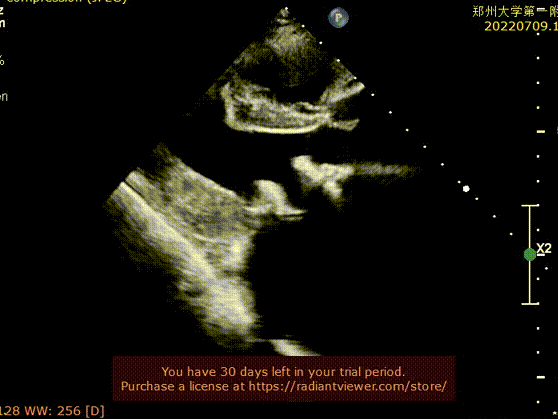

该患者为69岁老年男性,于2013年3月因风湿性心脏病二尖瓣重度狭窄合并冠心病进行冠状动脉搭桥手术联合二尖瓣生物瓣置换术,此次因反复胸腔积液至当地医院予以纠正心衰药物治疗,超声检查提示人工二尖瓣狭窄并重度关闭不全,人工二尖瓣返流,左心房显著增大。

瓣膜释放后显示人工瓣膜位置良好、微量瓣周漏,跨二尖瓣平均压差为5mmHg,顺利完成手术。